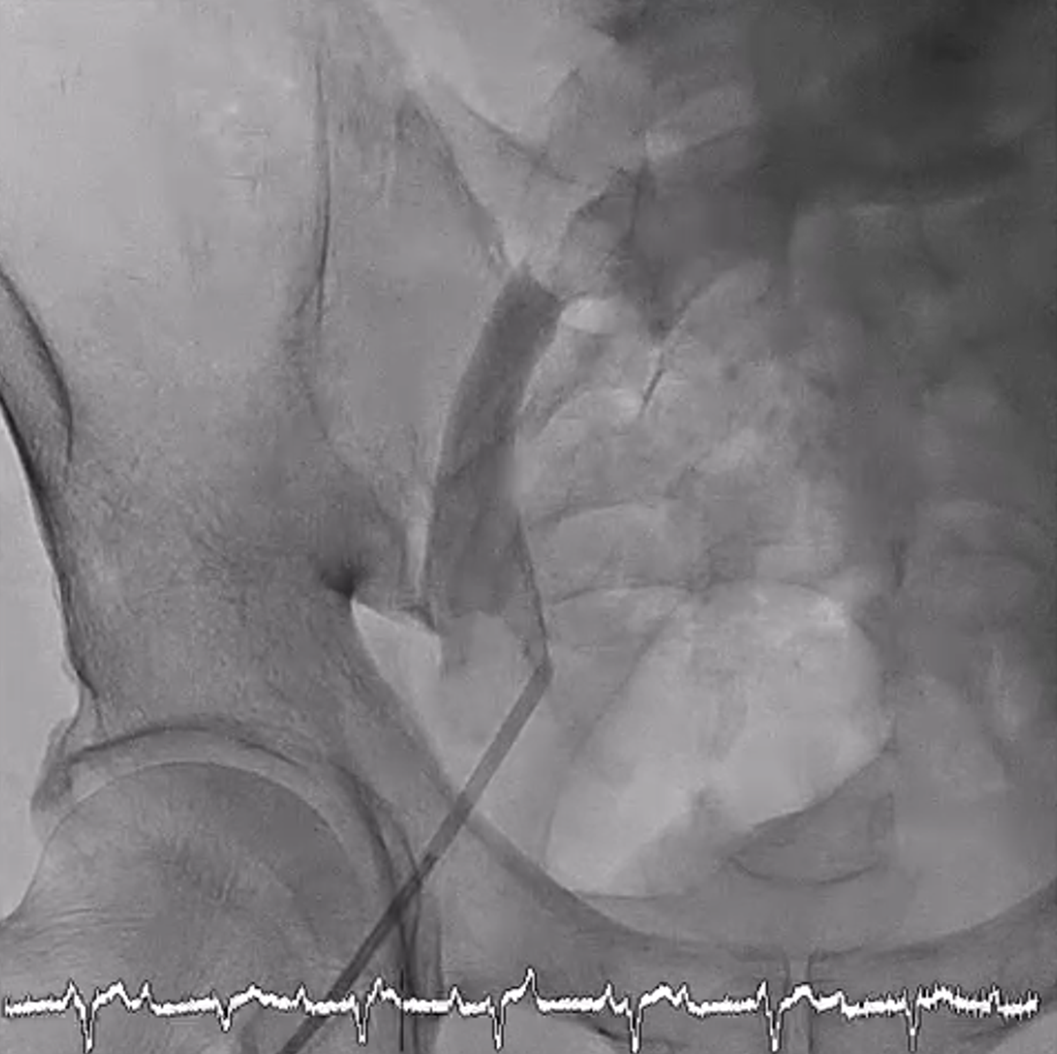

Ultrasonography-guided venous access was obtained at the right common femoral vein, and a 6F sheath was inserted. However, a 0.035-inch J-wire failed to be advanced beyond right iliac vein, with great resistance encountered. A contrast venogram was performed, which showed the appearance of a filling defect at the right common iliac vein and the venous course crossing to the left side (Figure 1, Video). Anomaly involving the lower limb veins was suspected, and the procedure was suspended.